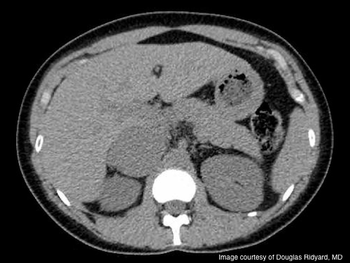

A 46-year-old male underwent a left laparoscopic radical nephrectomy for a cT1b renal cell carcinoma. Intra-operatively, a rent in the descending mesocolon was made during bowel mobilization but was not closed. Subsequently, the patient presented to the emergency room 4 days later with complaints of sudden onset sharp abdominal pain and nausea. A non-contrast computed tomography scan was obtained. What is the diagnosis?